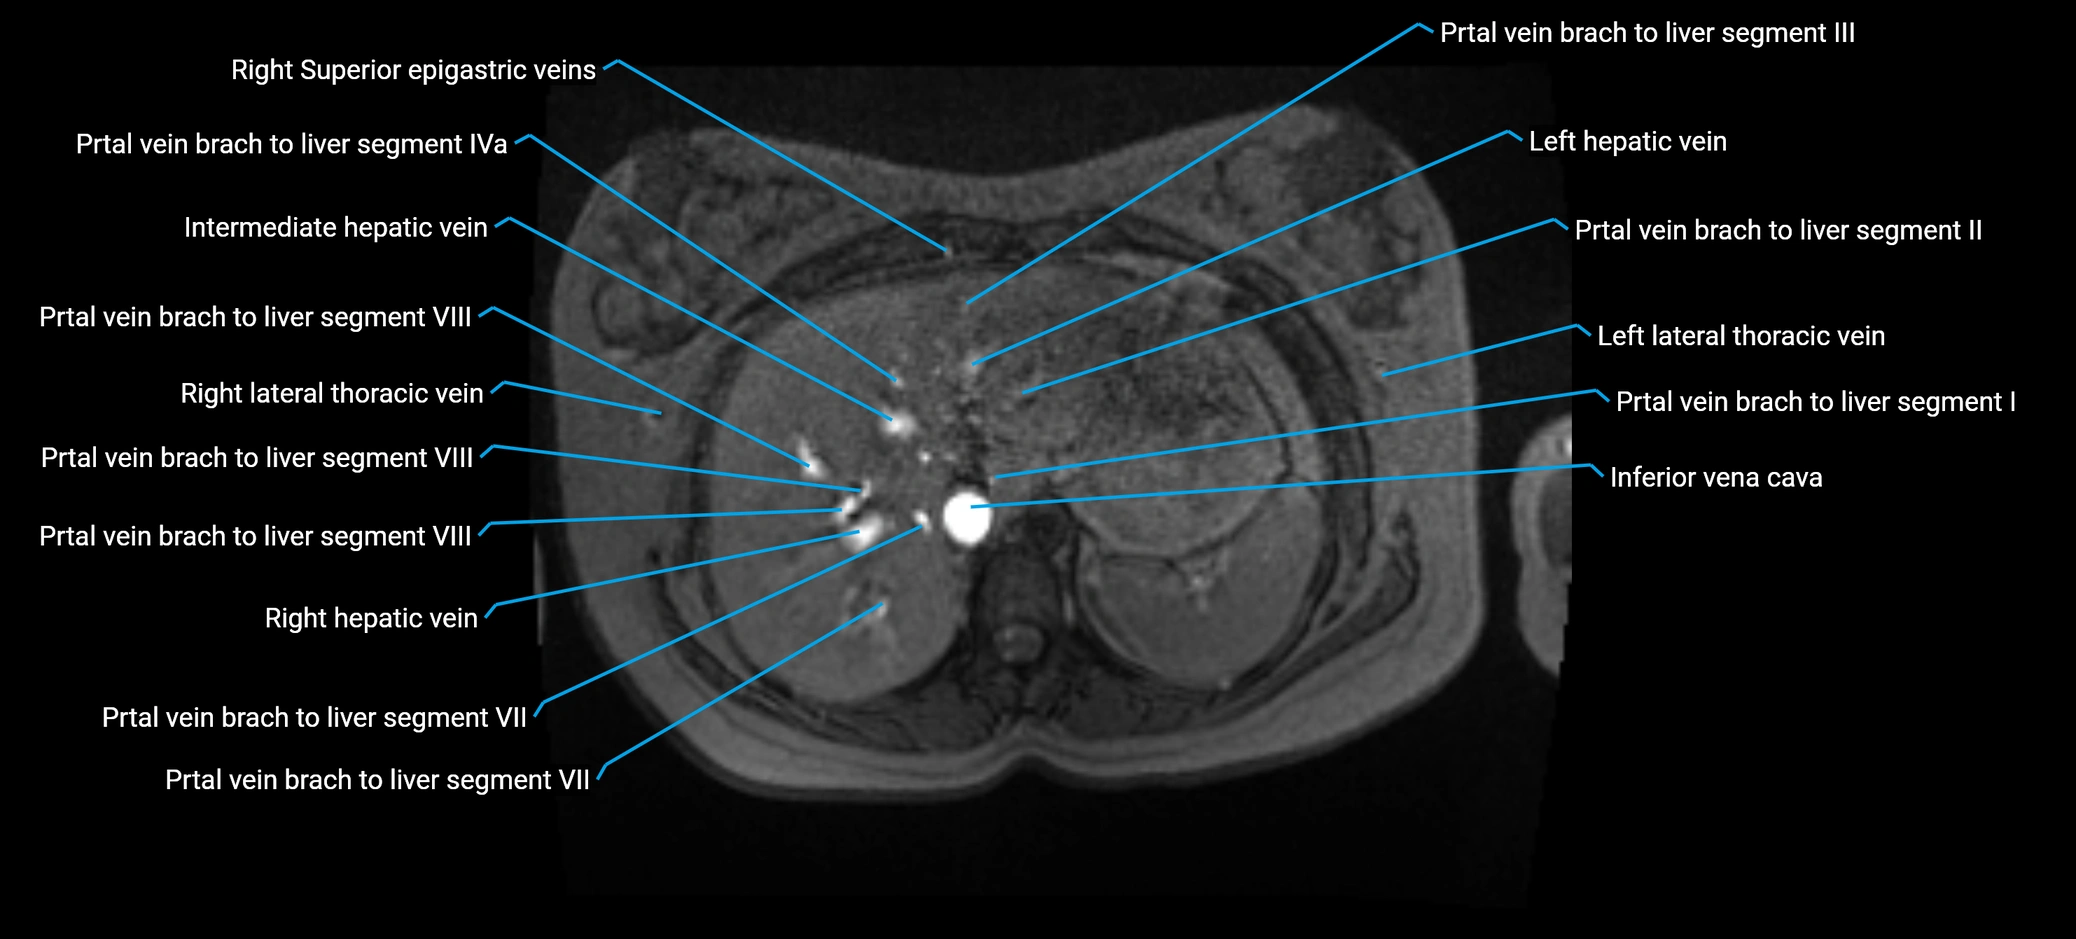

MRV TOF (Time-of-Flight MR Venography):

• Appears as a bright, high-signal vascular channel representing flowing blood

• Clearly shows branching pattern of right portal vein into anterior and posterior branches

• Best in coronal or axial reconstructions for segmental mapping

• No need for contrast, relies on flow-related enhancement

MRI image

image